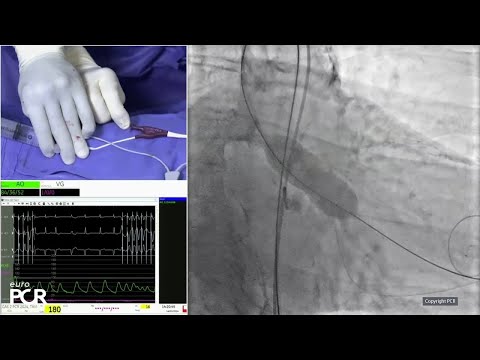

Episode 26 | The Latest Advances in TAVR: How to Significantly Reduce Conduction Disturbances